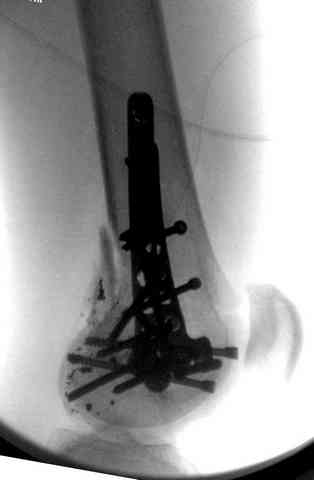

2 внутрисуставной перелом дистального бедра с удалением пули

Условием для обязательного удаления пули считаем ее внутрисуставное расположение из-за возможного сатурнизма, или когда во время операции она без труда удаляется, а также поверхностно расположена.